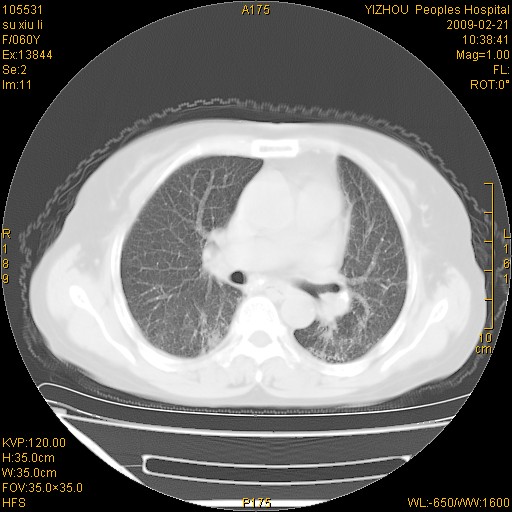

标题: CT18259:两肺间质纤维化?

女,60岁,反复咳嗽1月。

两肺支扩,以肺为著合并双肺较广范纤维化病变。建议除外结核等病变。

间质性肺炎

符合间质感染,部分纤维化表现

特发性间质纤维化

特发性间质纤维化伴支扩!